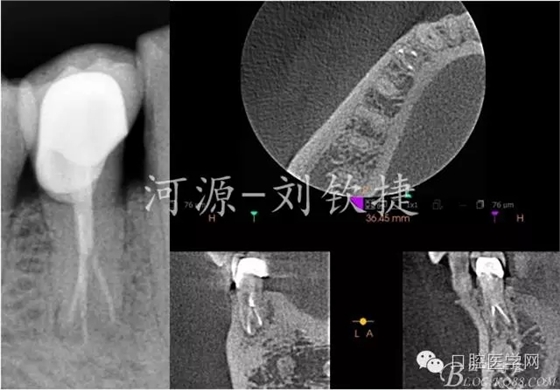

輔助檢查:X-Ray顯示44未做根管治療,根管影像在根中1/2突然消失,且明顯可見近遠(yuǎn)根,根尖區(qū)有模糊陰影;拆除冠修復(fù)體后CBCT顯示44C型根管,頰側(cè)1根,舌側(cè)2根,頰側(cè)頸1/3白色影像達(dá)髓腔??膳袛嘧畛蹙歪t(yī)的原因是楔缺導(dǎo)致的牙髓炎。